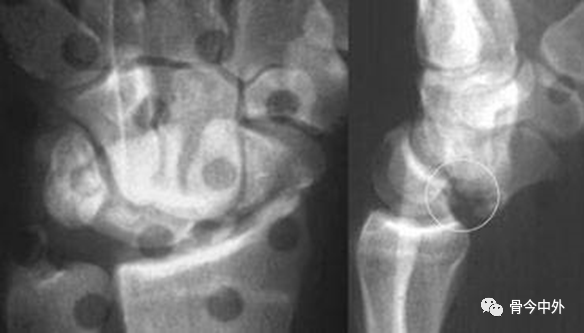

在腕关节侧位片上,一旦头状骨长轴骨偏离月骨和桡骨远端表面所形成的直线而向背侧成角或掌侧成角,即可诊断月骨周围脱位。

月骨周围脱位时虽然月骨半脱位造成一定程度的月骨倾斜角,但月骨仍保留在与桡骨远端表面所形成的关节内(图24A)。

在背掌位片上,腕骨的近侧列和远侧列重叠、弧线 II 和弧线 Ⅲ 在头状骨的位置中断,提示月骨周围脱位(图24B)。

图24 月骨周围脱位。(A)腕关节侧位X线片显示典型的相对于月骨的头状骨背侧移位,虽然月骨轻度掌侧旋转,但仍保留在与桡骨远端所形成的关节内。注意第三掌骨、头状骨与月骨和桡骨远端所形成的直线中断。在背掌位投照X线片上(B),月骨周围脱位表现为由弧 II 和弧 Ⅲ 的中断所造成的腕骨近侧列与远侧列的重叠。